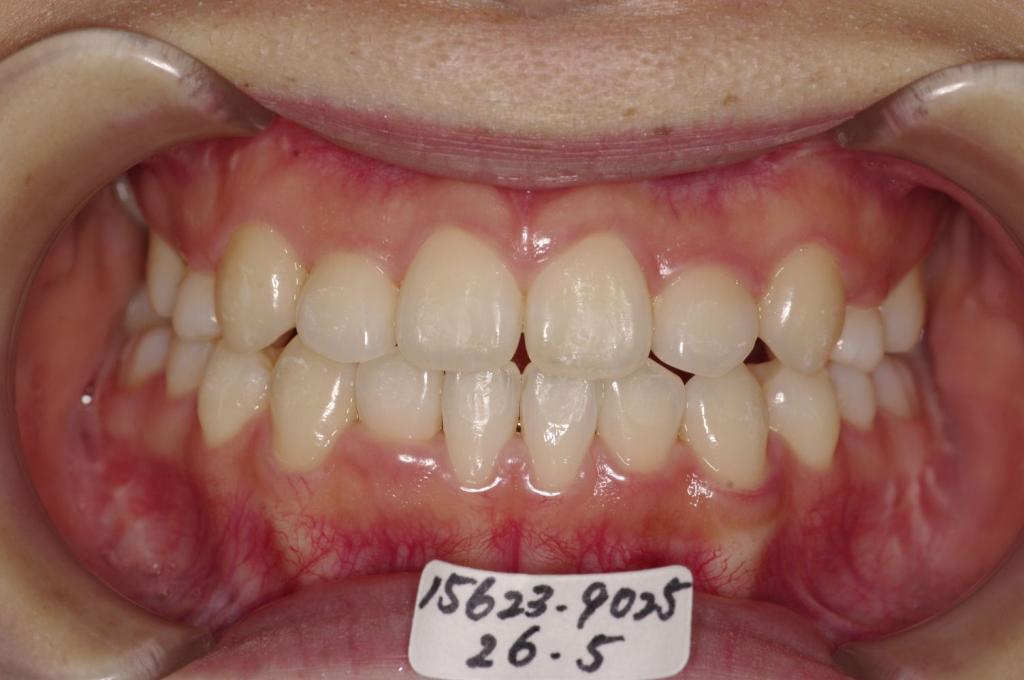

顎、顔の歪みの矯正治療

(治療期間、治療前後写真、治療方法、費用)WORKS